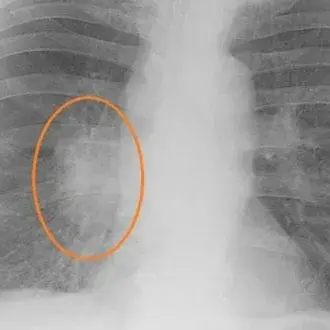

Затемнение в лёгких: что это такое и когда стоит беспокоиться?

Когда врач смотрит рентгеновский снимок легких и замечает затемнение, это еще не повод для паники, но и не тот случай, когда можно просто забыть...